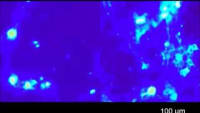

Search CHANNELS Aerospace Automotive Automated & Autonomous Vehicles Battery & Electrification Technology Defense Drone TV Electronics Manufacturing & Prototyping Materials Medical Motion Control RF & Microwave Technology Robotics & Automation Sensors & IoT Test & Measurement CHANNELS Aerospace Automotive Automated & Autonomous Vehicles Battery & Electrification Technology Defense Drone TV Electronics Manufacturing & Prototyping Materials Medical Motion Control RF & Microwave Technology Robotics & Automation Sensors & IoT Test & Measurement Aerospace & Defense Search Results Looking for Deep Brain Activation? Meet ImPULS Watch this video to learn more about an implantable piezoelectric ultrasound stimulator (ImPULS) that generates an ultrasonic focal pressure of 100 kPa to modulate the activity of neurons. Topics: Medical View the discussion thread. Transcript 00:00:06 [Music] [Music] a [Music] [Music] [Music]